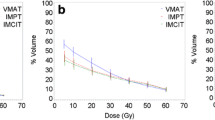

Evaluated plans for pancreatic adenocarcinoma (A) and for glioblastoma (B) patient cases are displayed in Fig. 1. The prescription dose and target optimization goals were achieved as shown in biological dose maps and the dose volume histograms (DVHs) outlined in panels (D). LETd maps, LETd profiles and LETd-volume histograms (LVHs) demonstrate that the maximum LETd for IMPT plans is placed outside of the target volume and extends into normal tissues. For the GTV, LETd values were around ∼40–65 keV/µm. In order to increase LETd in the target, LETd optimization feature was also investigated in Fig. 1 (IMPTLET). As observed from the LETd distribution, the inclusion of LETd-boosting allows LETd-escalation at the GTV, while having a minimum impact on the target dose coverage (see DVH for the clinical target volume, CTV). IMPTLET allowed an increase in the GTV minimum LETd from 55.1 keV/µm to 87.1 keV/µm, and from 38.4 to 48.6 keV/µm, for the glioblastoma and pancreatic adenocarcinoma cases, respectively. However, LETd optimization comes at the expense of an increase in the beam’s entrance biological dose. For the glioblastoma patient, for example, there could be an increase of up to 30% in the biological dose delivered to the skin directly exposed to the entrance channel. Additionally, for IMPTLET plans, normal tissue DVH highlights an increase of the volume in the middle range doses (20–30 Gy (RBE)) compared to standard IMPT.

For both glioblastoma and pancreatic cases shown in Fig. 1, SHArc led to an enhancement of the maximum LETd in the GTV up to at least 125 keV/µm, while the minimum GTV LETd values were 46.1 keV/µm and 47.2 keV/µm, respectively. The plotted LETd profiles further demonstrate that the maximum LETd for SHArc plans is concentrated in the central region of the tumour.

Maps of biological dose (DRBE) and LETd for IMPT, IMPTLET and SHArc plans for (A) pancreatic adenocarcinoma and (B) glioblastoma patient cases using carbon ions. For visualisation, the LETd values are displayed with a 5 and 20 Gy low-dose threshold, for glioblastoma and pancreatic cases, respectively. The white lines in the LETd map designate the LETd profiles presented in panel (C). (C) Profiles for LETd are presented highlighting the LETd range within the GTV for both cases. (D) DRBE- and LETd-volume histograms are shown for relevant organs of interest, for the IMPT (full line), IMPTLET (dashed line) and SHArc plans (dotted line). For the DVH plots (top row), the CTV is shown (orange), as well as either the body excluding the PTV or the brain excluding PTV (pink), for the pancreatic and the head case, respectively. In the LVH plots (bottom row), the GTV is shown for both cases (green), as well as the main OAR for each case (red): the gastrointestinal tract for the pancreatic adenocarcinoma and the ventricles of the brain for the case of the glioblastoma. For the pancreatic case, two lines are mostly indistinguishable for the OAR shown in both the DVH and the LVH, due to the nearly overlap between IMPT and IMPTLET volume histograms (i.e., full and dashed lines).

This comes at the cost of a low dose-bath as shown in the normal tissue DVHs. In terms of LETd in the OARs, SHArc could be particularly beneficial for pancreatic adenocarcinoma. In this case, the clinical beam arrangement results in higher LETd values towards the beam’s distal edge, thus directly leading to high LETd in the gastrointestinal tract, which is posterior to the tumour. With SHArc shifting the high LETd towards the tumour’s centre, there is a direct reduction of the near-maximum LETd in the gastrointestinal tract. Specifically, SHArc lowers the maximum LETd in the gastrointestinal tract to 47.5 keV/µm compared to 88.0 keV/µm and 83.0 keV/µm found for the IMPT and IMPTLET plans, respectively. For the glioblastoma case, in which opposite fields are considered as the standard, the reduction of the near maximum LETd in the surrounding OAR, i.e., the brain ventricles, is less pronounced. Nonetheless, there is still an observed decrease in the LETd5%, from 88.4 keV/µm to 79.7 keV/µm.